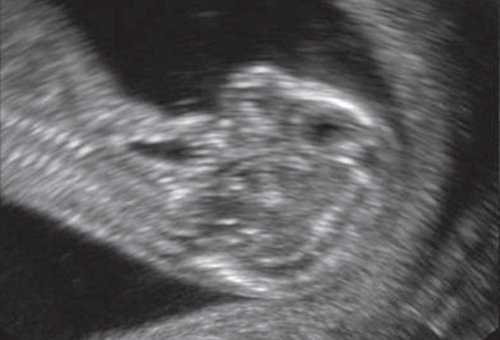

При эхографии в срок 13 недель 3 дня фетометрические параметры плода соответствовали гестационной норме, толщина воротникового пространства составила 1,5 мм; длина костей носа - по 2,5 мм. При трансвагинальном сканировании были обнаружены: затылочное энцефалоцеле размерами 7,4х3,5х3,7 мм (рис. 1), полидактилия кистей (рис. 2), увеличенные кистозно-измененные почки: правая - 28,5х21,3 мм; левая - 26,4х18,7 мм (рис. 3). Объем амниотической полости был нормальным для данного срока.

Синдром Меккеля. Диагностика и прогноз при синдроме Меккеля